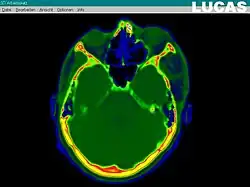

Segmentace obrazu je metoda, nebo spíše skupina metod postavených na různých principech, digitálního zpracování obrazu, která slouží k automatickému rozdělení vlastního obrazu na oblasti se společnými vlastnostmi a které obvykle mají nějaký smysluplný význam. Typickým cílem segmentace obrazu je identifikace popředí a určení oblastí v obraze odpovídajícím významnému prvku zachycené scény.

Výsledky segmentace jsou využitelné například v počítačovém vidění, zpracování lékařských obrazových dat (Medical Imaging) nebo při analýze obrazů získaných při dálkovém průzkumu Země.